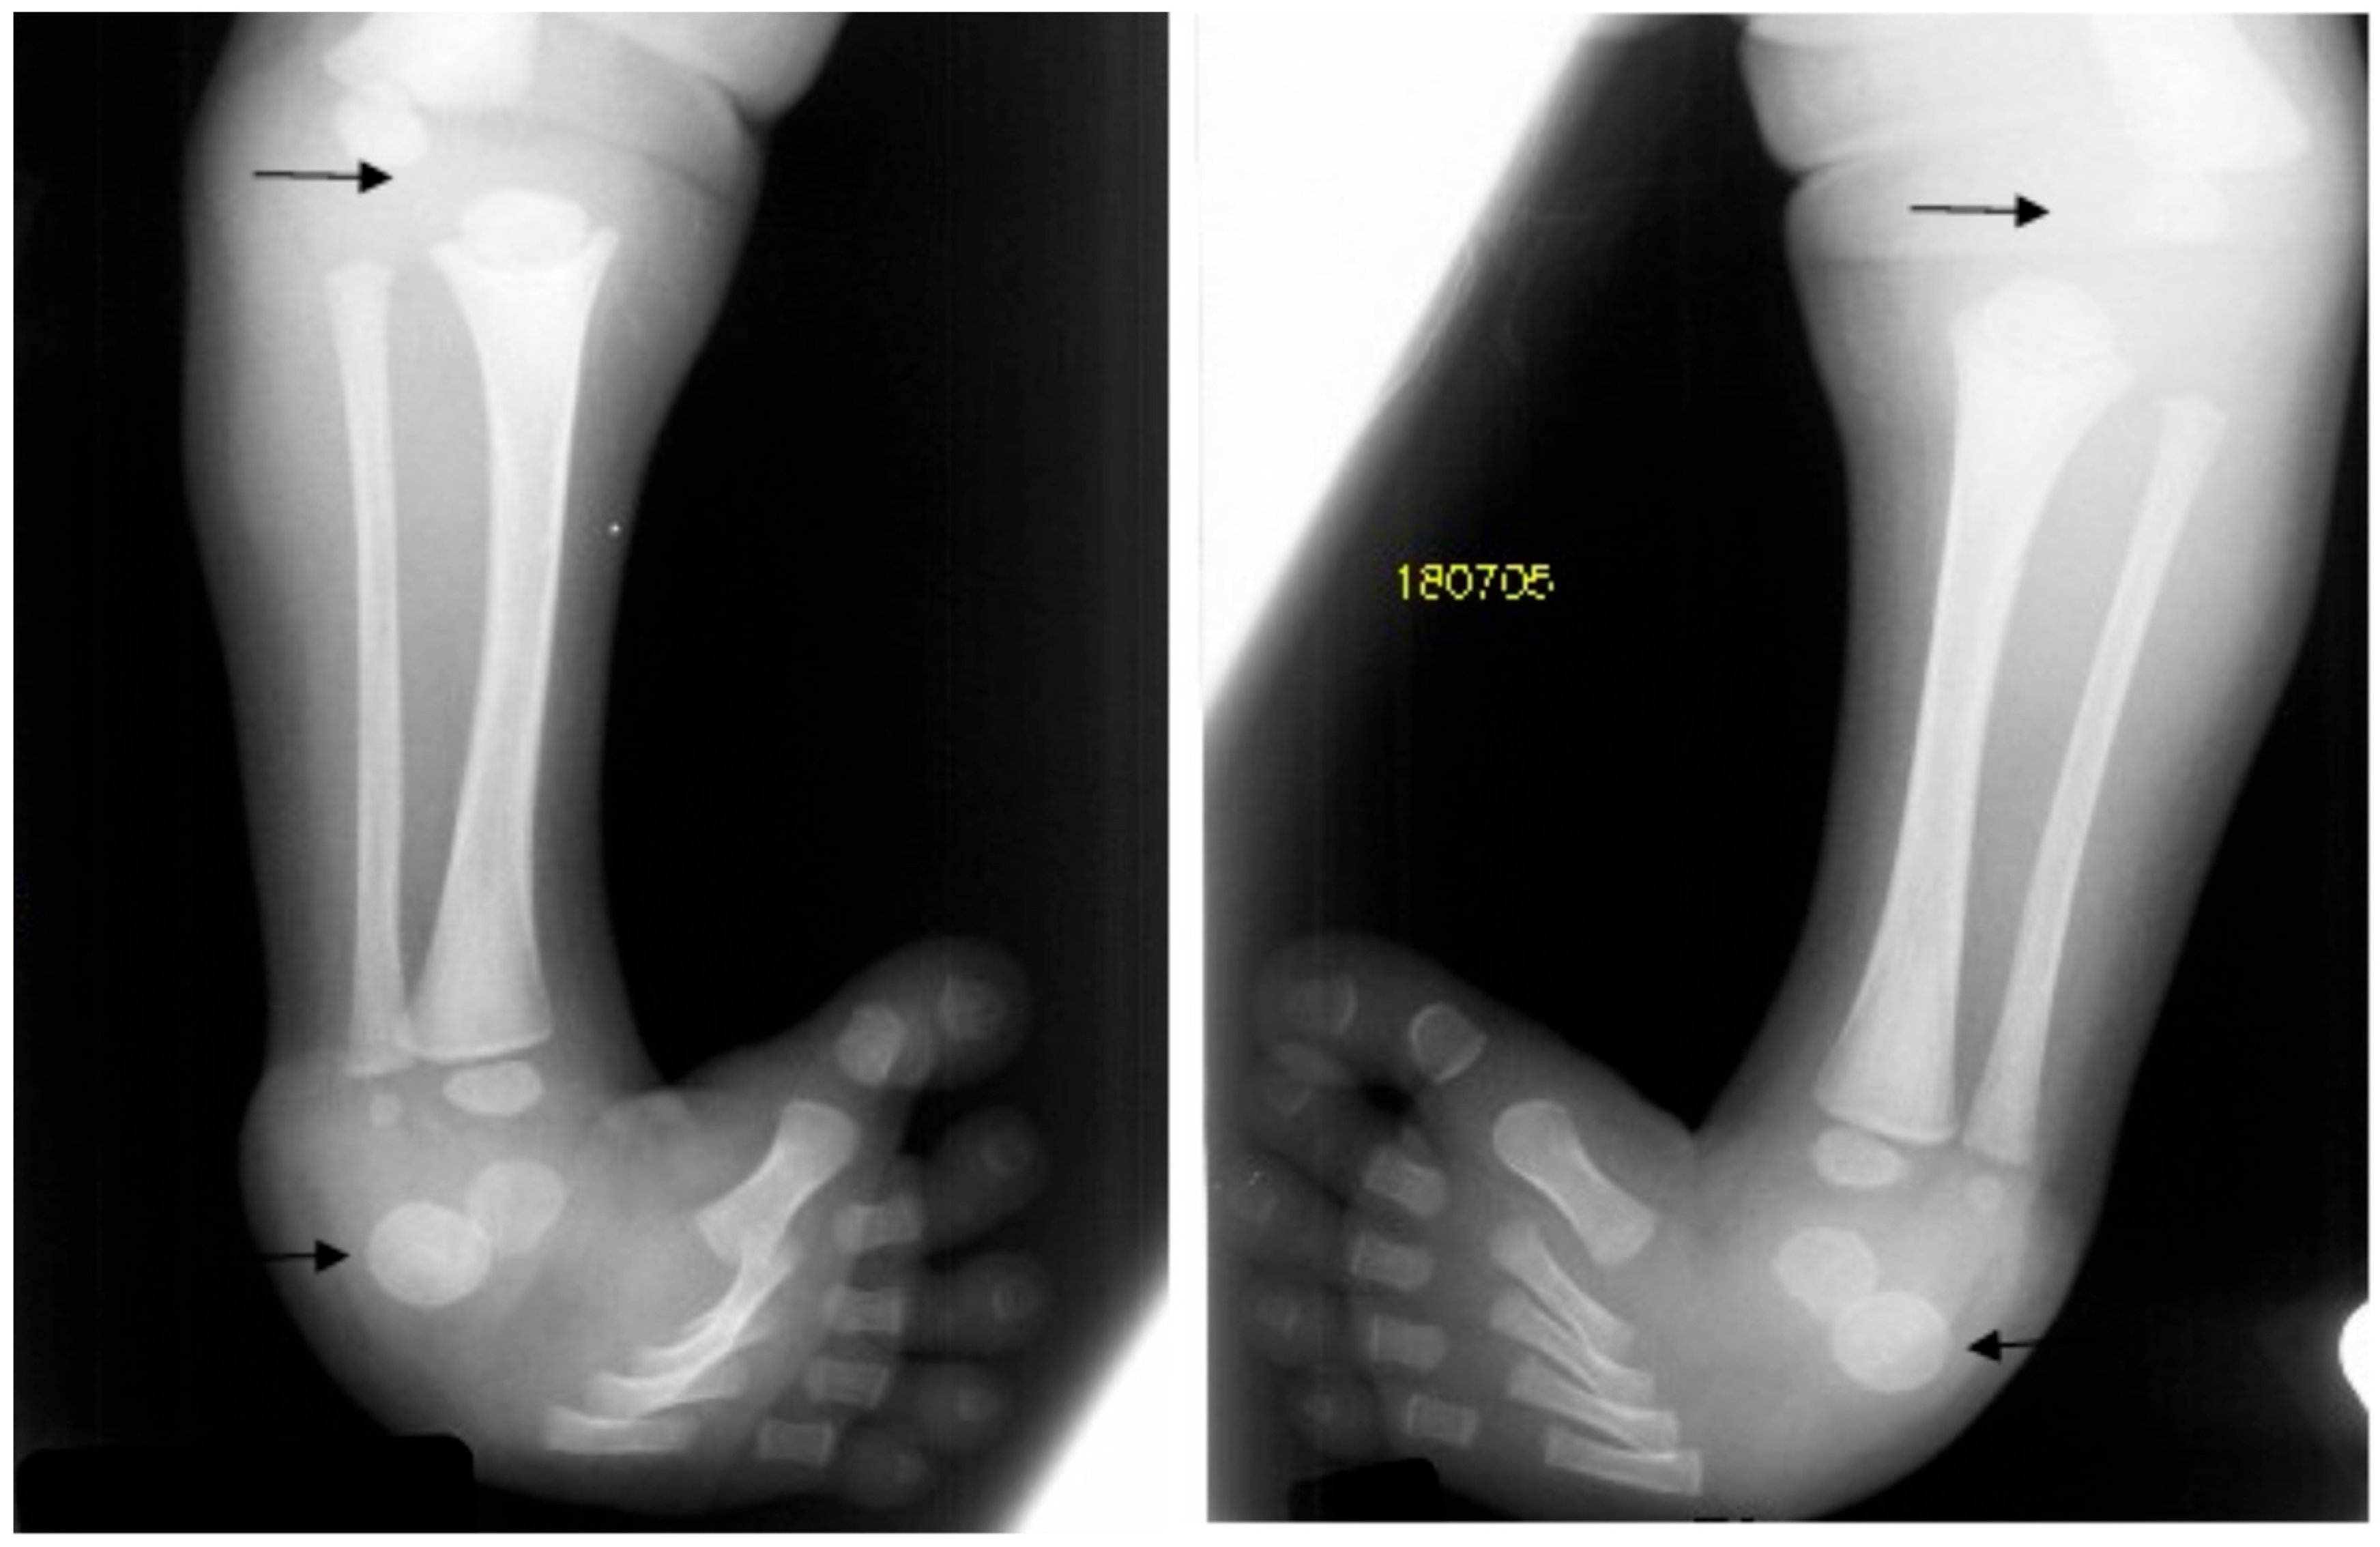

In these children, dysmorphic facial features were evident, which encompassed distinctive facial features, frontal bossing, and a flattened nasal bridge giving the facial phenotype of a dish-like facies. Our orthopedic strategy is based upon detailed clinical and radiological phenotypic characterization. Radiological phenotypic interpretations have been organized for all children by referring to 3D CT scan. In a lateral skull radiograph of a 7-month-old boy with Larsen syndrome, one can note brachycephaly, frontal bossing, and marked disproportionate small facial bones in comparison with a large cranium and dysplastic cervical spine, osteopenia of the lambdoid bones causing downward bulging, and prominence of the occipital bone associated with progressive thinning of the squamous part of the occipital bone (arrow). One can also note the cervical kyphosis (arrow) AP hand radiograph of a 3-year-old boy with Larsen syndrome showing retarded bone age, expansion of the distal ends of the shortened metacarpals, a thumb proximally placed, and the presence of accessory bone adjacent to the distal third metacarpal-phalangeal bone (arrow). One can also see the delta phalanx of the middle metacarpophalangeal bone of the fifth finger (arrow) (b) (Figure 1a,b). The AP pelvis radiograph of a 7-month-old girl with Larsen syndrome showed bilateral hip dislocation associated with maldevelopment of a severely dysplastic acetabulum and dysplastic capital femoral epiphysis (a). The AP pelvis radiograph of a 3-year-old boy with Larsen syndrome showed bilateral hip dislocations (severe acetabulo-femoral dysplasia) (Figure 2a). The AP pelvis radiograph of a 7-month-old girl with Larsen syndrome showed bilateral hip dislocation associated with maldevelopment of a severely dysplastic acetabulum and dysplastic capital femoral epiphysis (a). The AP pelvis radiograph of a 3-year-old boy with Larsen syndrome showed bilateral hip dislocations (severe acetabulo-femoral dysplasia) (Figure 2b). AP knees radiograph of a 5-month-old boy with Larsen syndrome showing bilateral knee dislocations (arrows) associated with under tubulation of the tibae and fibulae. Note the fragmented/deformed epiphyses and that the right tibia is medially subluxated. Note bilateral talipes equinivarus associated with double ossifications of the calcaneus (arrows) (Figure 3).

Figure 3.

AP knees radiograph of a 5-month-old boy with Larsen syndrome showing bilateral knee dislocations (arrows) associated with under tubulation of the tibae and fibulae. Note the fragmented/deformed epiphyses and that the right tibia is medially subluxated. Note bilateral talipes equinivarus associated with double ossifications of the calcaneus (arrows).